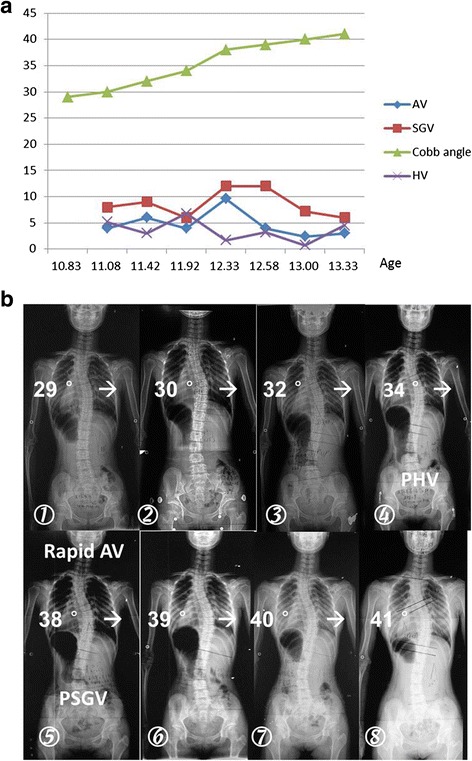

PHV was identified in 18 (29.0 %) and PSGV in 37 (59.7 %) cases, respectively. The Chi-square test revealed that PSGV contributed more to the occurrence of highest AV than PHV (P = 0.001). A demo case was shown in Fig. 2.

A demo case illustrating the influence of variations of growth velocity in relation to fluctuation of curve progressive velocity. a: Longitudinal curves of height velocity, spinal growth velocity, angle velocity and Cobb angle were constructed respectively. a & b: peak angle velocity occurred simultaneously with PSGV but not PHV